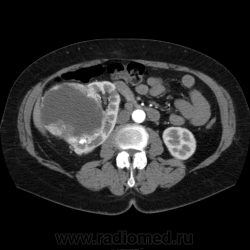

Солитарное кистовидное образование правой почки с неравномерно утолщенными стенками, у узлами в капсуле, накапливающими контраст. Фасция Гарота справа тяжистая. По классификации - киста 4-й категории, крайне велика возможность малигнезации. Может, показалось вовлечение парааортальных лимфоузлов?

В 1986 г. M.A. Bosniak создал “рабочую” классификацию кистовидных образований почек, которая позволяет предположить доброкачественность или злокачественность кистозных образований при распределении их по радиологическим критериям на 4 основные категории. Образования I и II категорий являются заведомо доброкачественными и поэтому нуждаются в динамическом наблюдении или, по показаниям, в лечебной пункции со склеротерапией под контролем УЗИ или КТ. Образования III категории могут быть как доброкачественными, так и злокачественными, а образования IV категории – кистозные почечноклеточные раки.

IV категория – поражения явно злокачественные, обычно кистозные почечно-клеточные карциномы. Основными симптомами кистозной опухоли при КТ являются: неправильная форма кисты, негомогенность структуры образования с участками некроза, деформация почки, нечеткая граница между кистой и паренхимой почки, плотностные показатели могут быть выше, чем в кистах (+20…+40 Н), т.е. близкие к плотности почечной паренхимы. Капсула имеет неравномерную толщину, часто обызвествлена по периферии. Возможна визуализация дополнительных фокусов образования (кажущееся увеличение образования в размерах и изменение его конфигурации) после введения контрастного вещества. Но самым важным симптомом является увеличение плотности внутреннего содержимого после внутривенного введения контрастного вещества. Часто на серии срезов удается выявить эндофитные гребневидные фестончатые разрастания, выступающие в просвет кистозной полости. Особенно хорошо этот мягкотканый васкуляризированный компонент опухоли проявляется при внутривенном контрастировании

Всё верно, я тоже пользуюсь данной классификацией по Босняку, кистозно-солидное образование правой почки я отнёс к 4 категории, нужно отметить, что преобладает кистозный компонент, но солидный компонент довольно приличный и значительно накапливает контрастное вещество до 80-90HU, четко капсулу образования не отграничить. Ко всему этому в паренхиматозную фазу четко дифференцируются единичные парааортальные и паракавалльные л/узлы. С большей степенью вероятности в данном случае cr почки. Пациентка на следующей неделе будет госпитализирована для верификации.

Описание изменений, выявленных при микроскопическом исследовании: опухоль представлена крупными альвеолярными структурами из светлых, оптически пустых клеток с мелкими гиперхромными ядрами, опухоль частично инфильтрирует капсулу почки, полностью прорастает стенку почечной лоханки, образуя полиповидные структуры. Одиночные опухолевые эмболы в сосудах почки. Отдельно присланный узел представлен тканью почки с опухолевым узлом, строение которого соответствует выше описанной опухоли. В воротах почки патологических образований не найдено. Во всех исследованных лимфоузлах (6 шт.) метастазы опухоли с замещением всей ткани лимфоузлов.

Патоморфологическое заключение: массивный светлоклеточный почечно-клеточный рак почки с частичной инфильтрацией капсулы, прорастанием в ЧЛС, опухолевыми эмболами в сосудах, множественными метастазами в забрюшинные лимфоузлы (6 шт